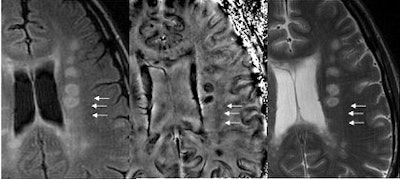

SWI offers a way to image the effects of stroke in terms of bleeding and changes in local oxygen saturation. Here, we show a case in which all other imaging methods failed to find the stroke. Very small amounts of iron can be detected with SWI. Bleeds otherwise totally invisible to conventional methods become visible with SWI.

| Left, conventional high resolution (TE = 40 msec) gradient-echo magnitude image shows nothing. Right, the SWI filtered phase image shows where the stroke took place. Image courtesy of E. Mark Haacke, Ph.D., Wayne State University, Detroit. |